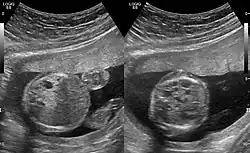

Congenital pulmonary airway malformation in a fetus, ultrasound at 19 weeks -sagittal. Stomach top right of image, heart displaced to bottom left of image (anatomically on the right side of fetus.)

Congenital pulmonary airway malformation in a fetus, ultrasound at 19 weeks - transverse. Stomach on left image; heart on right image: displaced to right by cystic mass